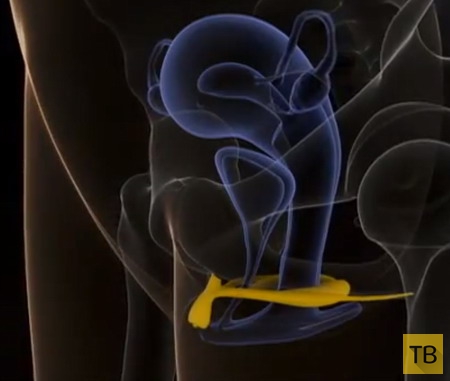

К сожалению, только в 2009 г. французская исследовательница доктор Одиль Бюиссон (Dr Odile Buisson) и доктор Пьер Фольде (Dr. Pierre Foldès) предоставили медицинскому сообществу первые трехмерные УЗИ стимулированного клитора. В течение трех лет они работали над этим проектом без какого бы то ни было должного финансирования. Благодаря им мы теперь понимаем, как пещеристая ткань клитора наполняется кровью и охватывает влагалище – настоящий прорыв, который показывает, что то, что раньше считалось вагинальным оргазмом, на самом деле является внутренним клиторальным оргазмом.

Внутренний клитор в эрегированном состоянии

Внутренний клитор в эрегированном состоянии